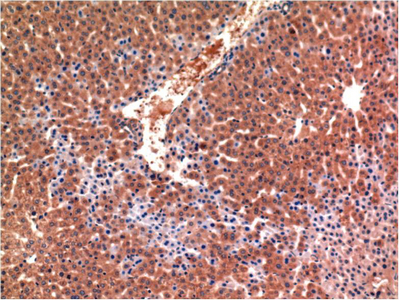

Caspase-3 mouse Monoclonal Antibody(4B8)

Application

| IHC-P |

| Dilution | IHC-P~~IHC 1:100-200 |

| Tissue Location | Highly expressed in lung, spleen, heart, liver and kidney. Moderate levels in brain and skeletal muscle, and low in testis. Also found in many cell lines, highest expression in cells of the immune system. |